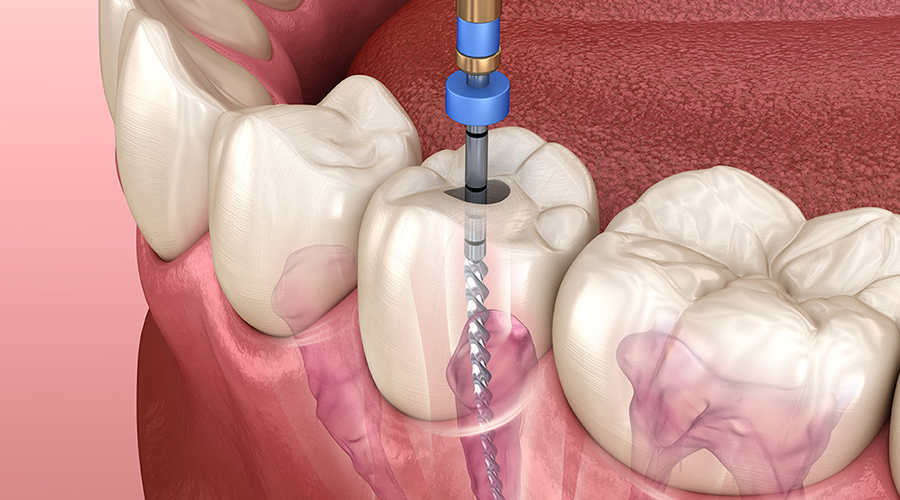

The best root canal dentist in Paschim Vihar operates from the top notch and highly advanced dental care clinic located in Paschim Vihar. Braces and root canal specialist applies the braces and do the root canals perfectly and flawlessly while allowing the patients to receive very less or no pain. For more details visit : https://www.essencedental.in/root-canal-treatment/